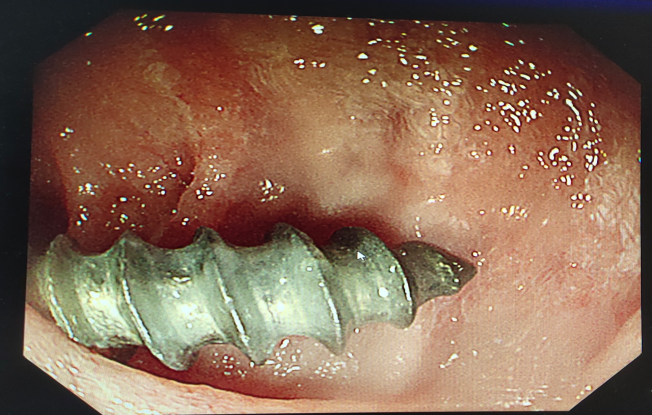

- 内镜下的骨片 -

在急诊科、麻醉科及手术室医护人员的多科协助下,李中跃主任医师将嵌顿于食管上的 2 cm 尖锐骨片,用鼠齿钳夹住并运用一定手法后顺利取出。